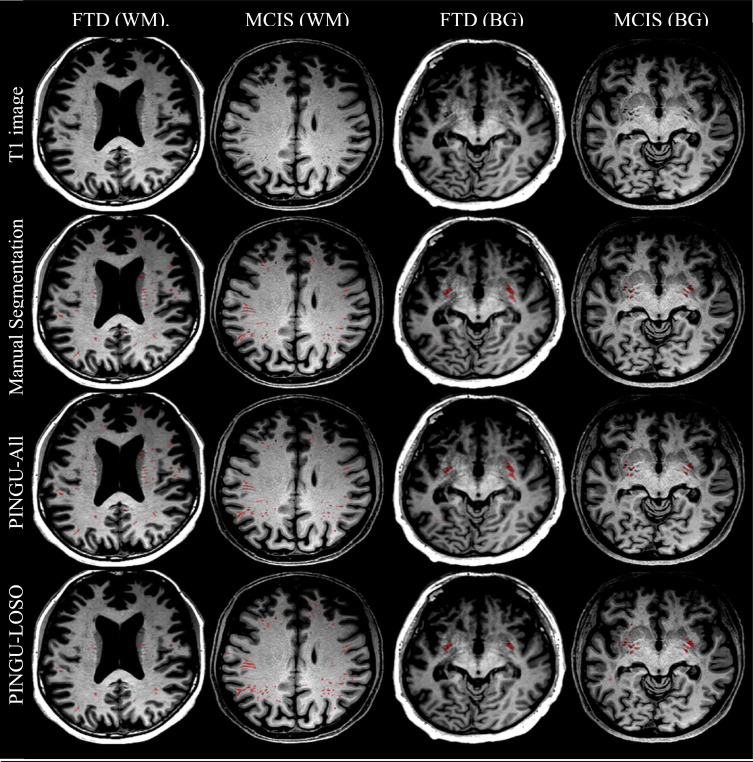

图1.PINGU-All和PINGU-LOSO在T1图像上的叠加,并与“高质量”数据集(MCIS)和“低质量”数据集(FTD)的手动分割进行比较。显示切片是根据手动分割中白质(WM)和基底神经节(BG)中PVS体积最大的切片自动选择的。